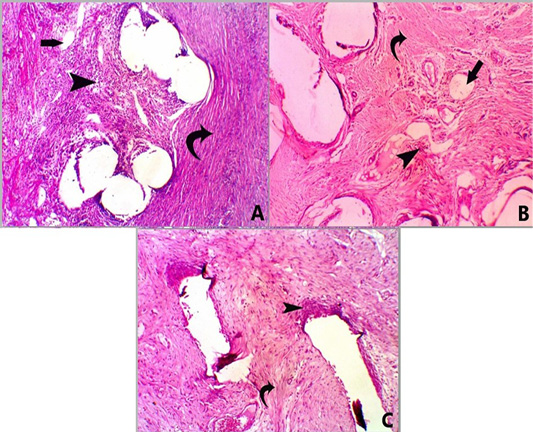

Figure 3

A photomicrograph of H and E stained sections for all groups at 28 days post-surgery. Group A, showing mesh surrounded by moderate infiltration of mononuclear inflammatory cells (score 3) (head arrow) with moderate fibrosis (score 3) (curved arrow) and minimal neovascularization (score 1) (straight arrow) X 100. Group B, showing mesh surrounded by mild infiltration of mononuclear inflammatory cells (score 2) (head arrow) with moderate fibrosis (score 3) (curved arrow) and minimal neovascularization (score 1) (straight arrow), X 100. Group C, showed mesh surrounded by mild infiltration of mononuclear inflammatory cells (score 2) (head arrow) with marked fibrosis (score 4) (curved arrow) X 100.